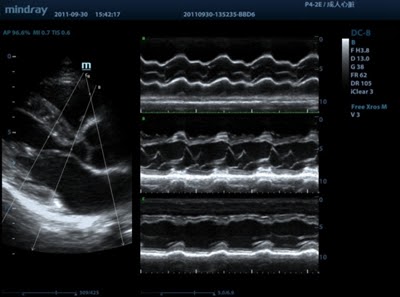

Free Xros M

Анатомический М-режим. Дает возможность выполнять точные анатомические измерения при помощи свободного размещения линий М-режима под любым углом. Получение большего количества диагностической информации за счет одновременного использования до 3 линий М-режима.